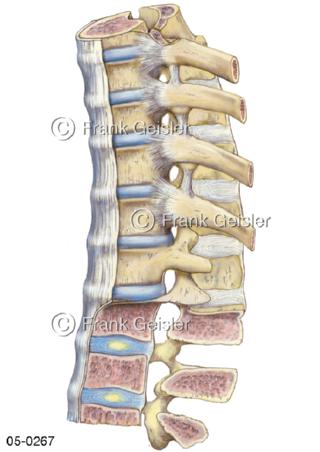

Bildergalerie Skelettsystem

Bilder zum Skelettsystem zeigen die Stützstruktur des menschlichen Körpers, die Knochen, eine besonders harte Form des Bindegewebes und Stützgewebes, welche das menschliche Skelett bildet, die Knochen des Stammes, der Extremitäten sowie der Gelenke